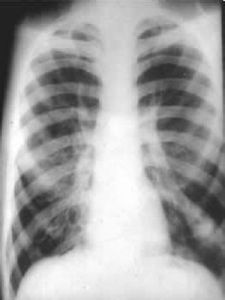

除肺、胸基礎疾病及急性肺部感染的特徵外,尚可有肺動脈高壓征,如右下肺動脈乾擴張,其橫徑≥15mm;其橫徑與氣管橫徑之比值≥1.07;肺動脈段明顯突出或其高度≥3mm;右心室增大征(圖2-3-3),皆為診斷肺心病的主要依據。個別病人心力衰竭控制後可見心臟外影有所縮小。